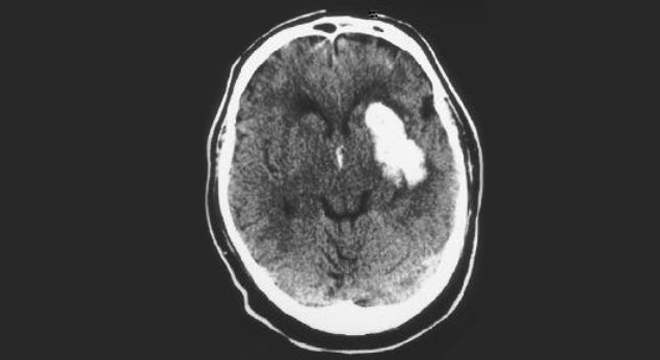

Von den Durchblutungsstörungen im Gehirn, welche als ischämischer Hirnschlag bezeichnet wird,  muss die Hirnblutung abgegrenzt werden, welche auch als  hämorrhagischer Hirnschlag bezeichnet wird. Aus den Symptomen lässt sich nicht beurteilen, ob ein ischämischer oder ein hämorrhagischer Insult (Hirnschlag) vorliegt. Bei einer massiven Blutung kommt es zu einer Druckerhöhung im Schädelinneren, welche innerhalb kurzer Zeit zum Tod führen kann.

Schlaganfall: Computertomographie MRI

• Computertomographie zum Ausschluss/Nachweis einer Hirnblutung, MRI